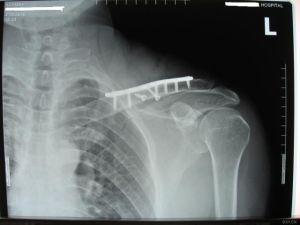

锁骨骨折有鼓包图片

锁骨骨折有鼓包图片,锁骨错位重叠长好图片

锁骨骨折手术图片

锁骨骨折钢板图片

锁骨骨折愈合图片